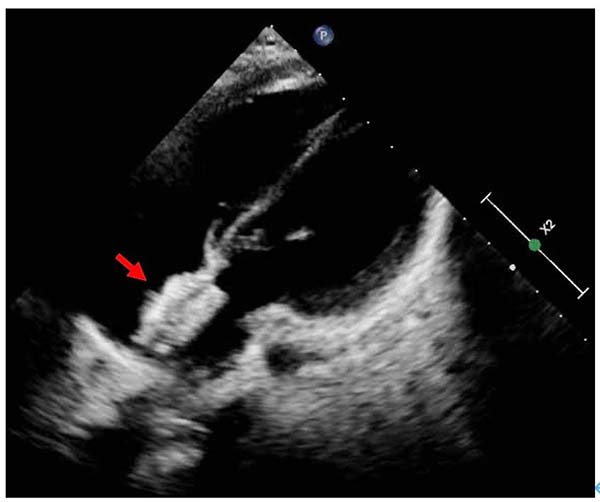

封堵器植入后超声影像

该患儿自幼确诊先天性心脏病、房间隔缺损,随访过程中发现心脏右心进行性增大。术前心脏超声评估显示缺损最大直径1.25cm,周边残端条件良好(均>7mm),符合介入封堵指征。经科室充分讨论并与患儿家长沟通后,团队决定采用全降解封堵器植入技术。

手术在我院特聘教授、上海交通大学医学院附属上海儿童医学中心李奋教授指导下,由主任医师韩波,副主任医师伊迎春、姜殿东、王静等共同完成,心脏超声科主任医师梁皓全程提供床旁心脏超声监测。术中成功建立输送轨道,在经胸心脏超声引导下精准植入一枚直径18mm的无Mark点全降解房间隔缺损封堵器,过程顺利,无并发症。